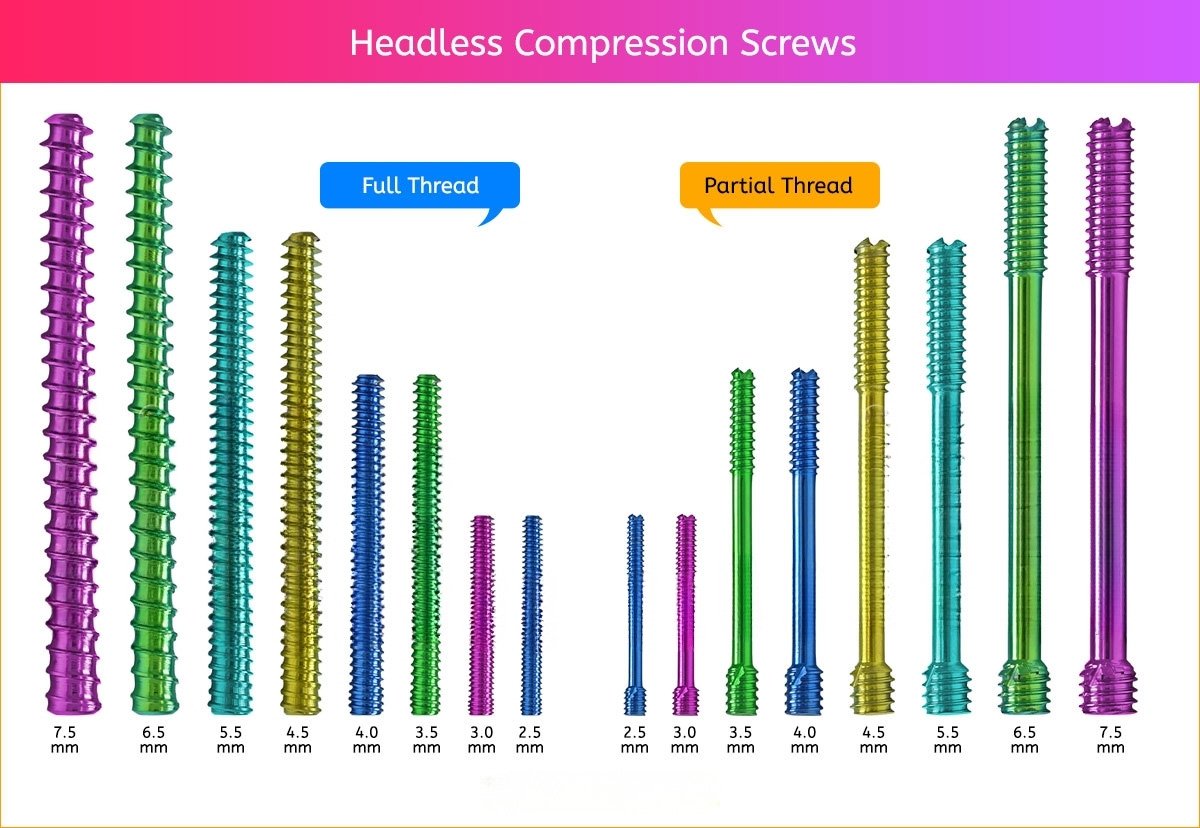

Headless Compression Screws

Headless Compression Screws

2.5 mm Headless Compression Screws

3 mm Headless Compression Screw

3.5 mm Headless Compression Screw

4 mm Headless Compression Screw

4.5 mm Headless Compression Screw

5.5 mm Headless Compression Screw

6.5 mm Headless Compression Screws

7.5 mm Headless Compression Screw

Headless Compression Screws Specification

- Two types of screws, Fully threaded, Partially threaded.

- Fully threaded: Fully threaded screw provides a higher holding force resulting in increasing stability.

Headless Compression Screws Sizes